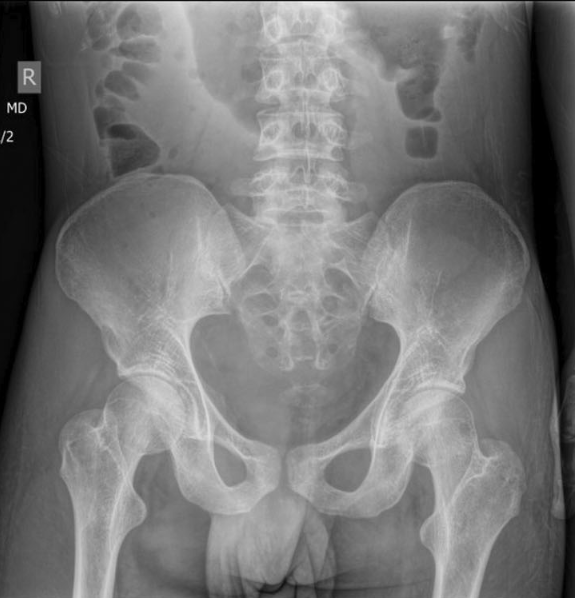

M Matar et al. J Pediatr Gastroenterol Nutr. 2026;82:487–494. Chronic nonbacterial osteomyelitis associated with pediatric inflammatory bowel disease: : A multicenter retrospective study from the Paediatric inflammatory bowel disease Porto Group of ESPGHAN

- CNO presented in 15 patients (33%) within 3 months of IBD diagnosis, and in additional 20 (44%) patients after IBD diagnosis; in 10 (22%) patients CNO preceded the diagnosis of IBD with a median time 46 (25–248) weeks

- 11 (24%) subjects displayed at least one additional extra-intestinal manifestations, including arthritis (6, 13%), erythema nodosum (4, 9%), sacro-ileitis (2, 4%), psoriasis (1, 2%), and pyoderma gangrenosum (1, 2%).

- Complications occurred in six patients and included vertebral collapse, bone fracture, and bone deformity. In eight (18%) subjects vertebral collapse was present already at the time of diagnosis.